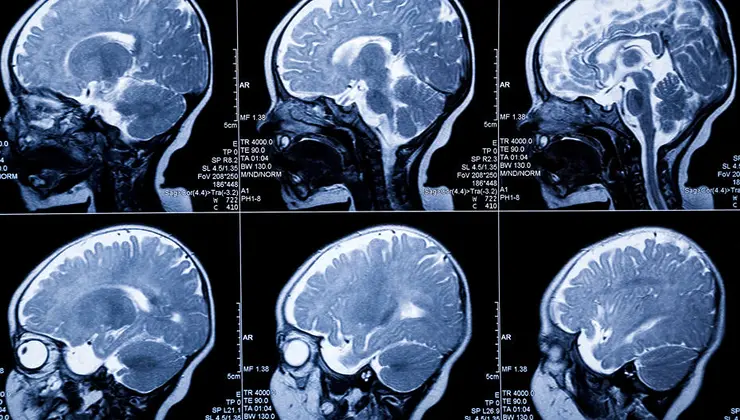

İngiltere’nin Cambridge Üniversitesi uzmanları, yenidoğanların beyinlerini yüksek hassasiyetle görüntülemek için yeni bir teknoloji geliştirdi.

“FUSION” adı verilen teknoloji sayesinde yenidoğanlarda oluşması muhtemel beyin hasarı erkenden tespit edilebilecek.

Doğum sırasında beynin yeterli oksijen alamamasıyla ortaya çıkan Hipoksi, bebeklerin hayat boyu engelli kalmasına yol açan nedenler arasında yer alıyor. Bu durum epilepsi ya da serebral palsi gibi durumlara da yol açabiliyor.

Mevcut izleme yöntemleri hasarın uzun vadedeki etkilerini öngörmekte yetersiz kalıyor. Erken teşhis ile tedavi ve destekleyici müdahalenin daha hızlı başlatılması hedefleniyor.